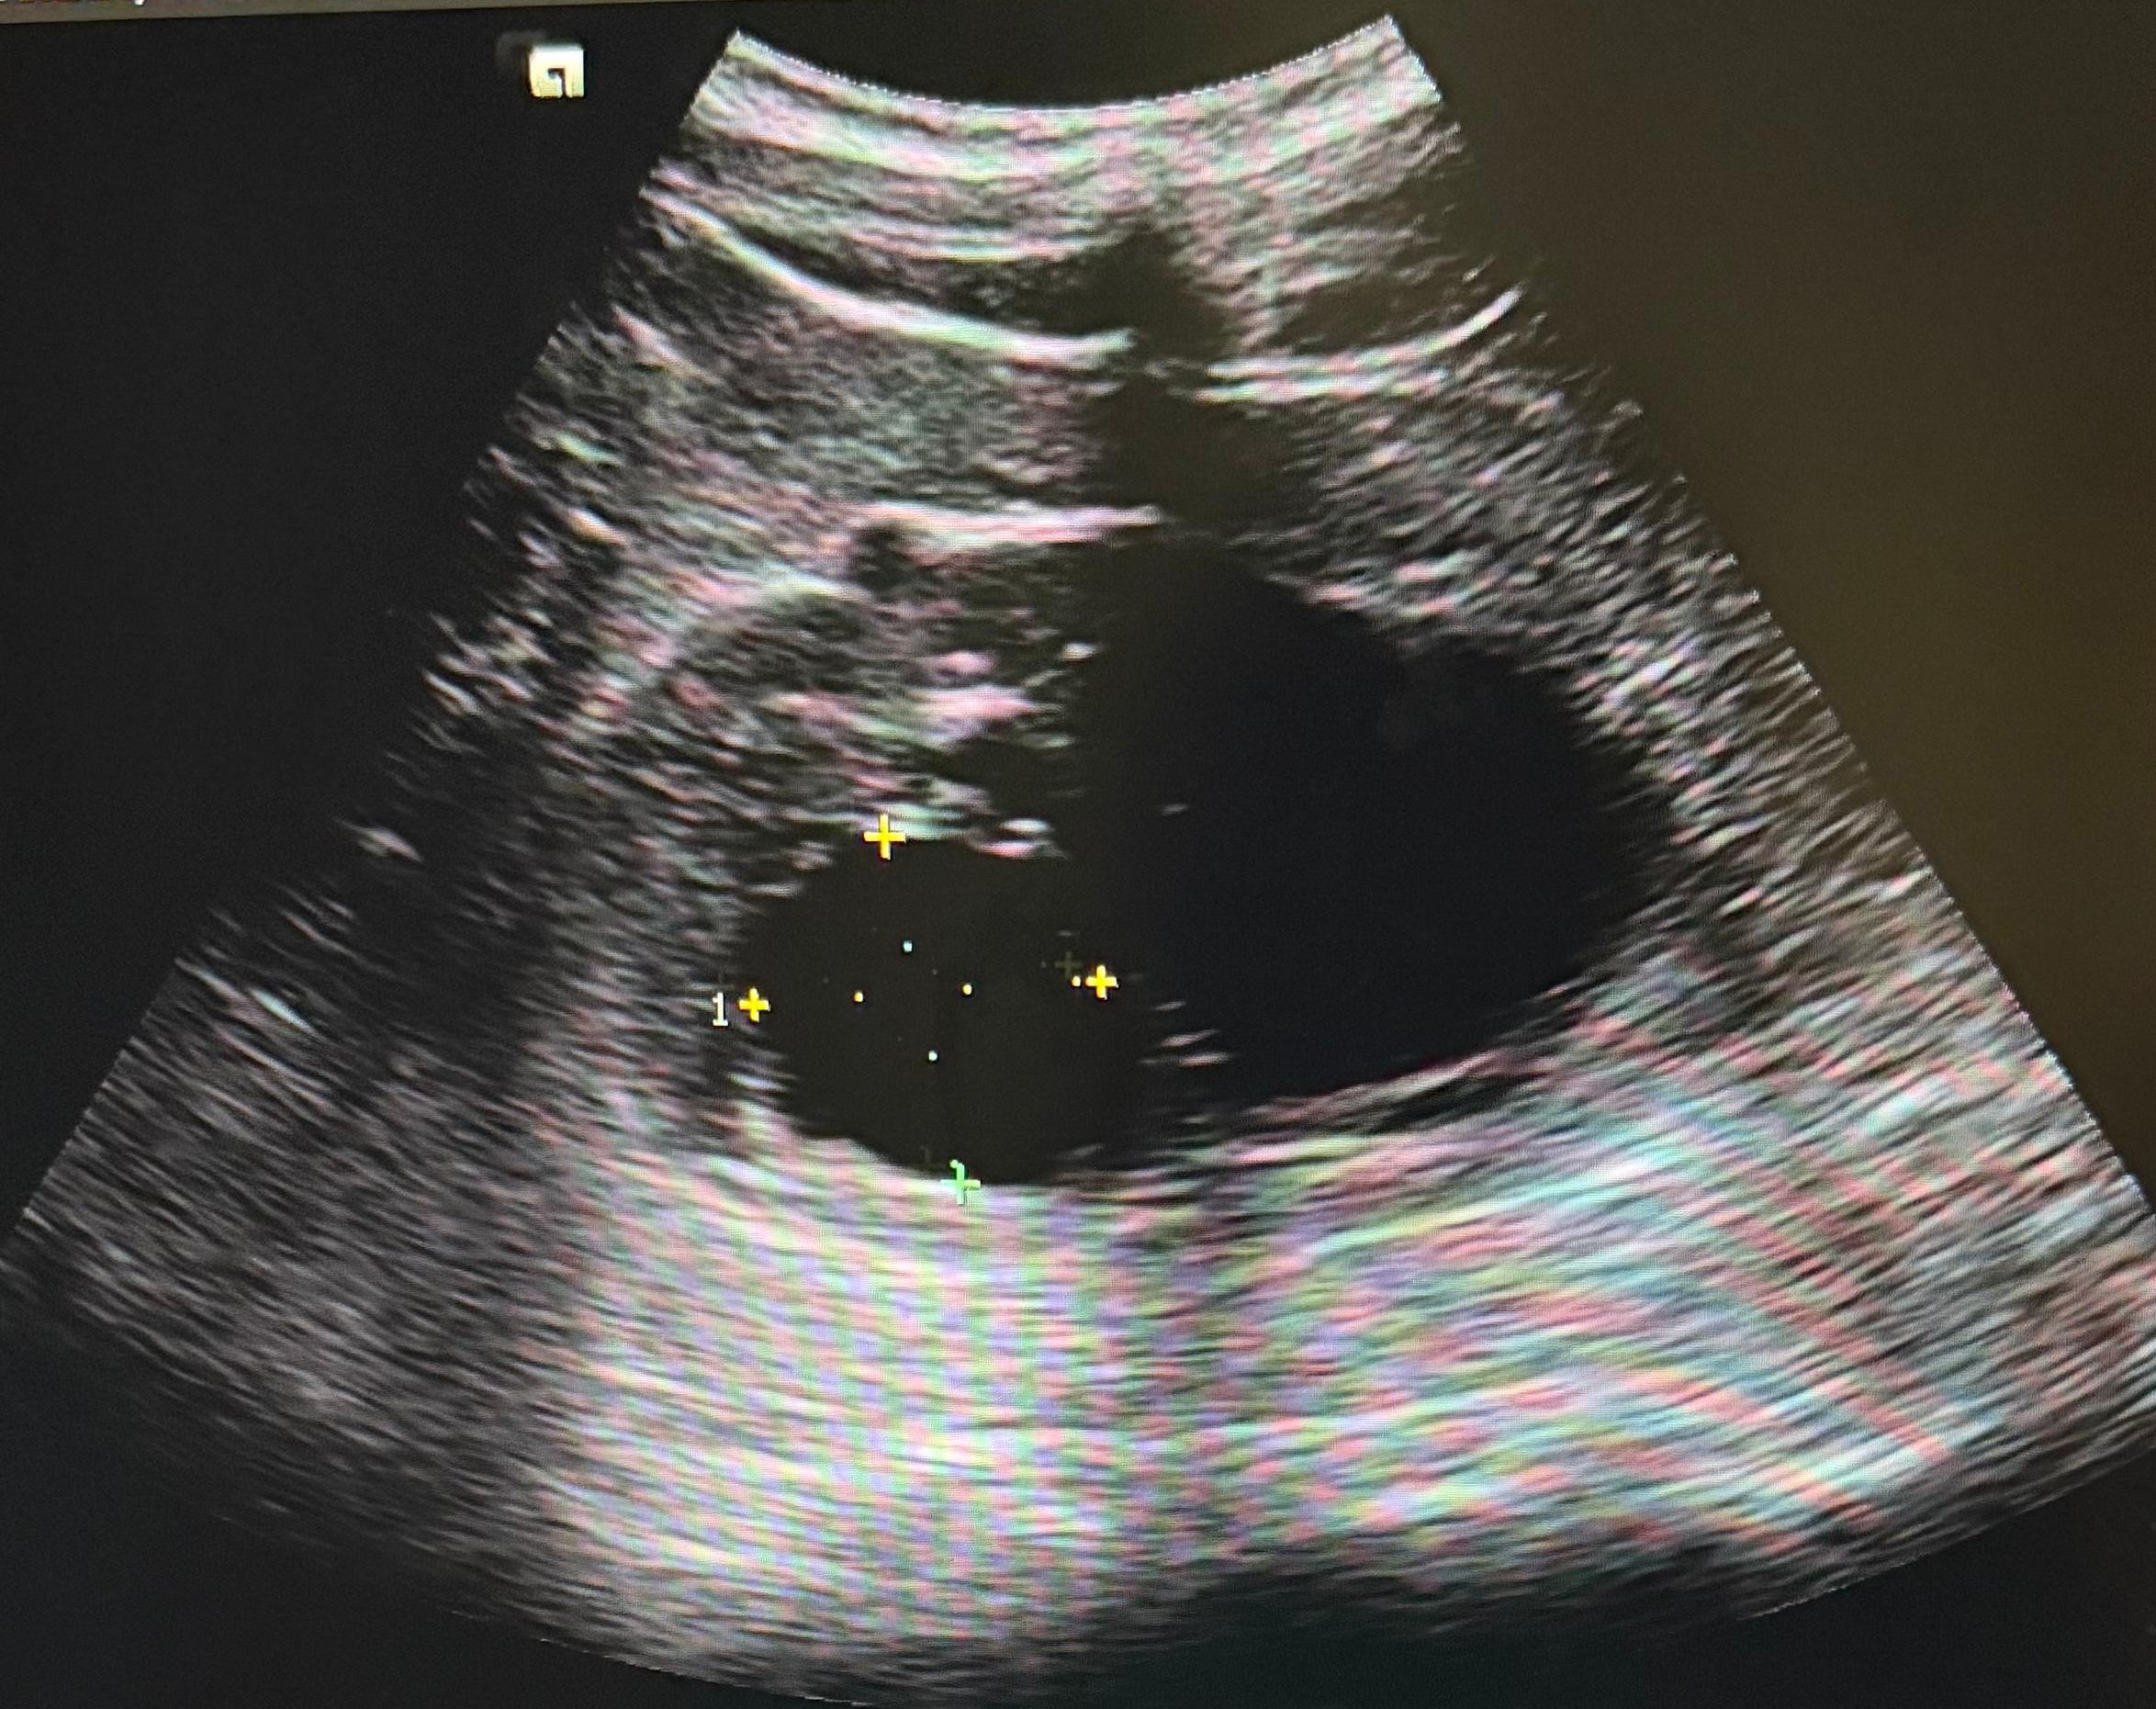

Hallazgos ecográficos

Se realiza ecografía abdominopélvica donde se visualiza vejiga sin alteraciones, próstata aumentada de tamaño con un volumen estimado de 59 cc. Como hallazgo incidental se objetivan ambos riñones aumentados de tamaño con varios quistes.

Juicio clínico: HBP y hallazgos compatibles con quistes simples vs poliquistosis renal.